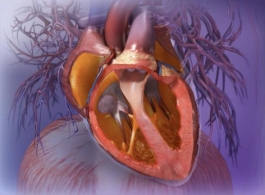

(一)X线平片心脏、大血管的正常投影

1后前位(正位)重点强调后前位胸片上心影轮廓的构成

IMG_29752021-06-07 14:34:48.7150002021-06-07 14:30:43.795000

1心右缘分为两段

上段为主动脉与上腔静脉的总投影

下段为右心房构成

2心左缘分为三段

上段为主动脉结

中段为肺动脉主干

下段由左心室构成